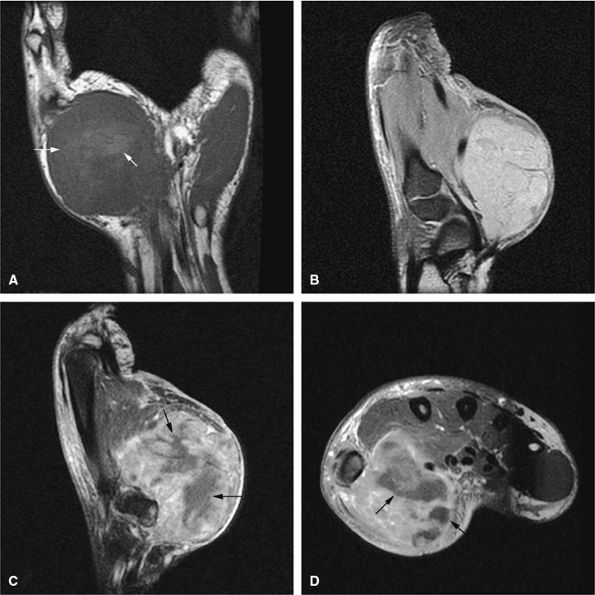

FIGURE 14-31 ● Undertubulation of the hips and knees in a patient with multiple hereditary exostoses. Exostoses (arrows) are seen on coronal (A) and axial (B) T1-weighted images of the hip. Sagittal proton density (C) and sagittal (D) and axial (E) fat-suppressed T2-weighted fast spin-echo images of the knee also demonstrate exostoses (arrows).